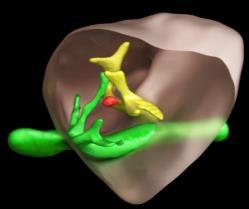

What if we could create a digital twin of the patient’s heart?

• Multiscale, Personalized Physiological Model of the patient’s heart

• Anatomy, Electrophysiology, Biomechanics (muscle contraction ), Circulation (ejection fraction, pressure dynamics)

• Mechanistic and statistical modeling

• Model is under our control

• Potential to test and prescribe best therapy for the patient – e.g., Cardiac Resynchronization Therapy

Ventricular Tachycardia Atrial Fibrillation Dyssynchrony – Heart Failure

Identify the ablation targets that will effectively terminate persistence AF? Identify the minimal ablation targets (catheter, RT) that will effectively terminate VT?

Cardiac radioablation –focus radiation using localization of VT exit

Anticipate the effects of CRT on patient’s cardiac function from preoperative data?